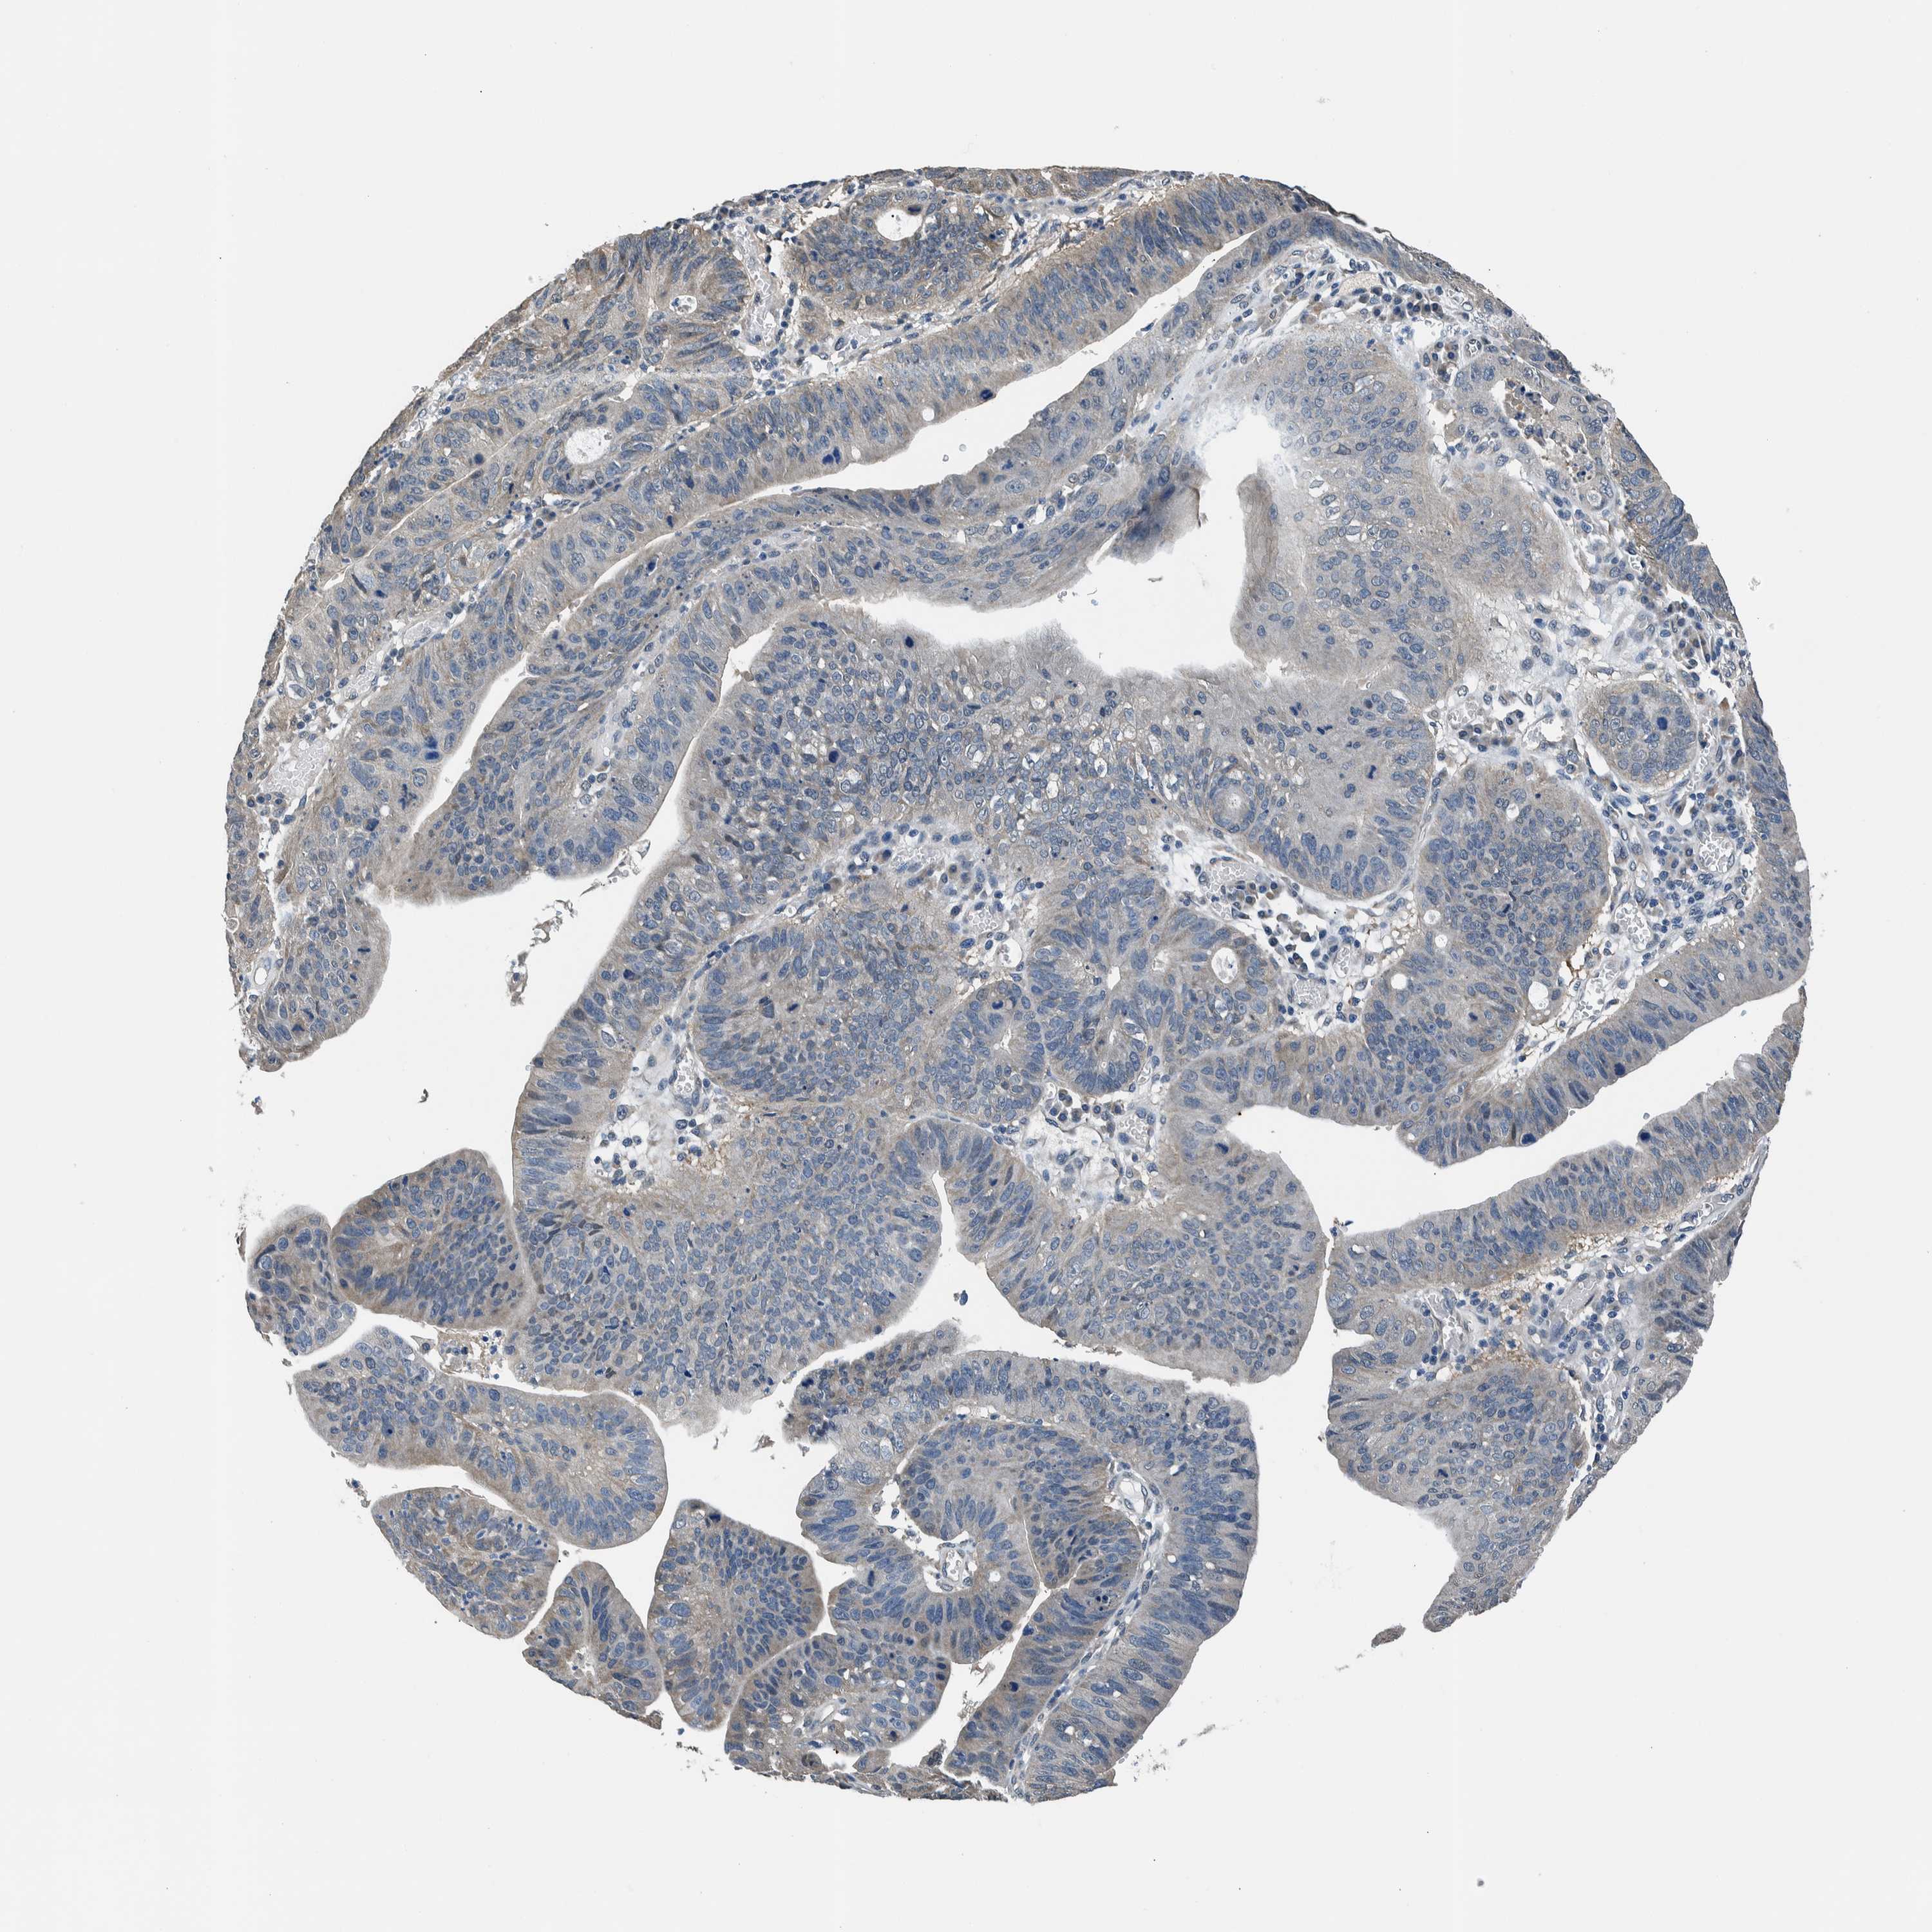

STOMACH CANCER - Protein expressioni

A mouse-over function shows sample information and annotation data. Click on an image to view it in a full screen mode. Samples can be filtered based on level of antibody staining by selecting one or several of the following categories: high, medium, low and not detected. The assay and annotation is described here.

Note that samples used for immunohistochemistry by the Human Protein Atlas do not correspond to samples in the TCGA dataset.

Antibody stainingi

Antibody staining in the annotated cell types in the current human tissue is reported as not detected, low, medium, or high, based on conventional immunohistochemistry profiling in selected tissues. This score is based on the combination of the staining intensity and fraction of stained cells.

Each image is clickable and will lead to virtual microscopy that enables deeper exploration of all samples and also displays staining intensity scores, fraction scores and subcellular localization as well as patient and tissue information for each sample.

Antibody HPA021284

Antibody HPA021417

Antibody HPA023261

Antibody HPA024312

Staining

High

Medium

Low

Not detected

Intensity

Strong

Moderate

Weak

Negative

Quantity

>75%

75%-25%

<25%

None

Location

Nuclear

Cytoplasmic/membranous

Cytoplasmic/membranous,nuclear

Adenocarcinoma, NOS